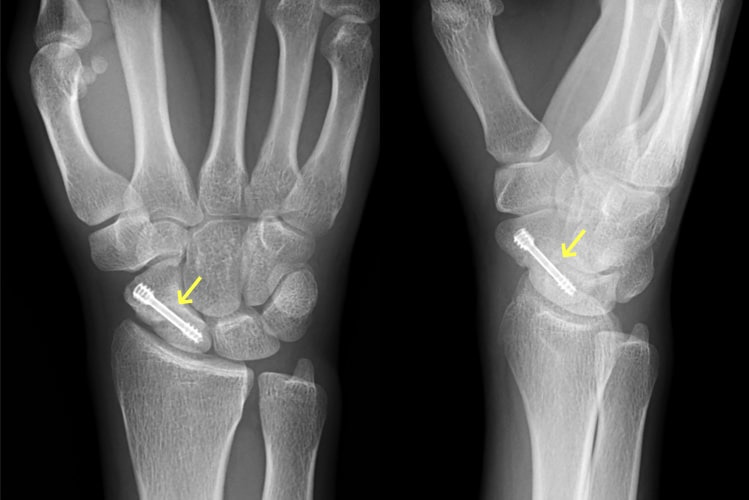

수술적 치료

- 볼라(locking) 플레이트 고정

- 조기 관절 가동 범위 운동(ROM)이 가능.

- 깁스 대신 가벼운 보조기 2 – 3주 착용 후 재활.